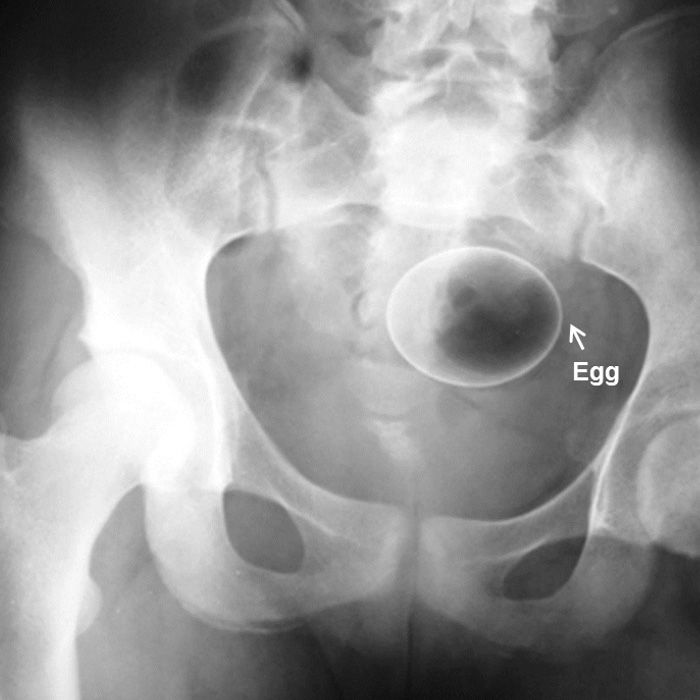

Dr Mohammad Taghi Niknejad

Yep. First I’m impressed that it’s still in one piece. Second, if it did break, that would be so painful coming out. Lastly, there are so many jokes about a certain celebrity’s “health line” that could be made.

I guess the egg beater was to try to get out the egg?